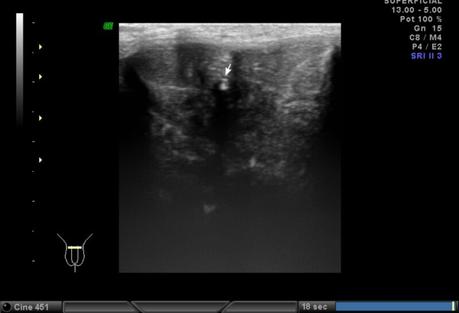

A nivel de base del pené, entre los cuerpos cavernoso y esponjoso en su porción central se observa la presencia de calcificación, que mide 2.2 mm. En tercio distal del pené, a nivel de cuerpos cavernosos con presencia de calcificación que mide 1.8 mm.

A NIVEL DE BASE Y TERCIO DISTAL DEL PENÉ, EN CUERPOS CAVERNOSOS CON PLACAS A RELACIÓN A ENFERMEDAD PEYRONIE.